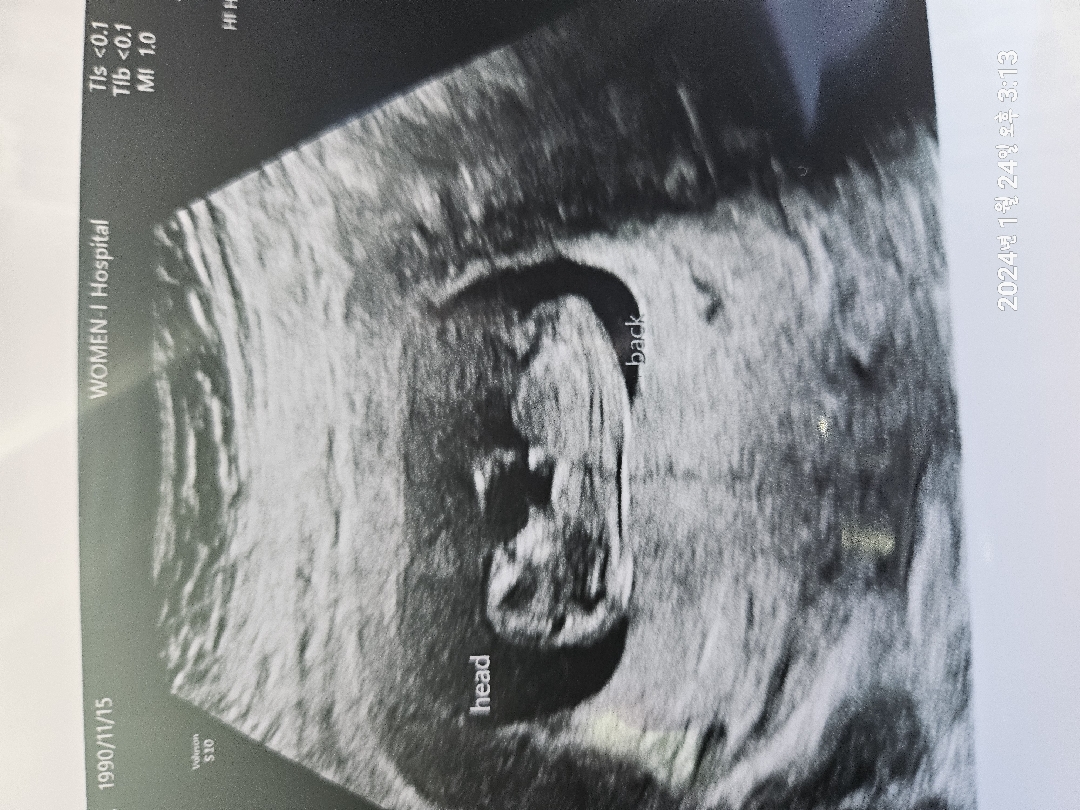

각도법으로 성별확인

각도법으로는 성별이 뭘로 보이셔용? 전 아들같은뎅..

저두 아들같아 보여요!!